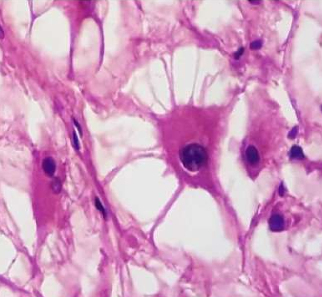

Cardiac neoplasm: Rhabdomyoma

- Large spider Cells

- Abundant cytoplasm, radial cytoplasmic strands extending to cell membrane

- May regress spontaneously